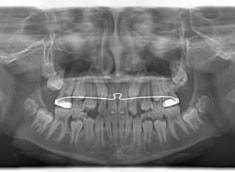

FX(フェイシャルアキシス)は85度なので東洋人の平均値に近く、下顎が前方に過剰成長するリスクは強くはありません。

しかしやはり上顎は劣成長で、下顎が優位な状態ではあります。

上下顎のギャップはありますが、顔面自体の幅径は良好な値を示していますので、スペース不足は拡大することによって解決できポテンシャルはあると考えられます。

左右の非対称もさほど強くありません。

骨年齢は実年齢よりも低めなので、今後下顎の旺盛な成長が見込まれます。

検査時のレントゲン分析では、上下顎の関係は、上顎の劣成長があり下顎前突傾向という値がでておりましたが、前歯ジャンプ後はフェイスマスクの効果もあり、上下顎の関係は正常化しています。

上顎が若干優位になっていますので、今後の下顎の成長のための貯金になっているくらいです。